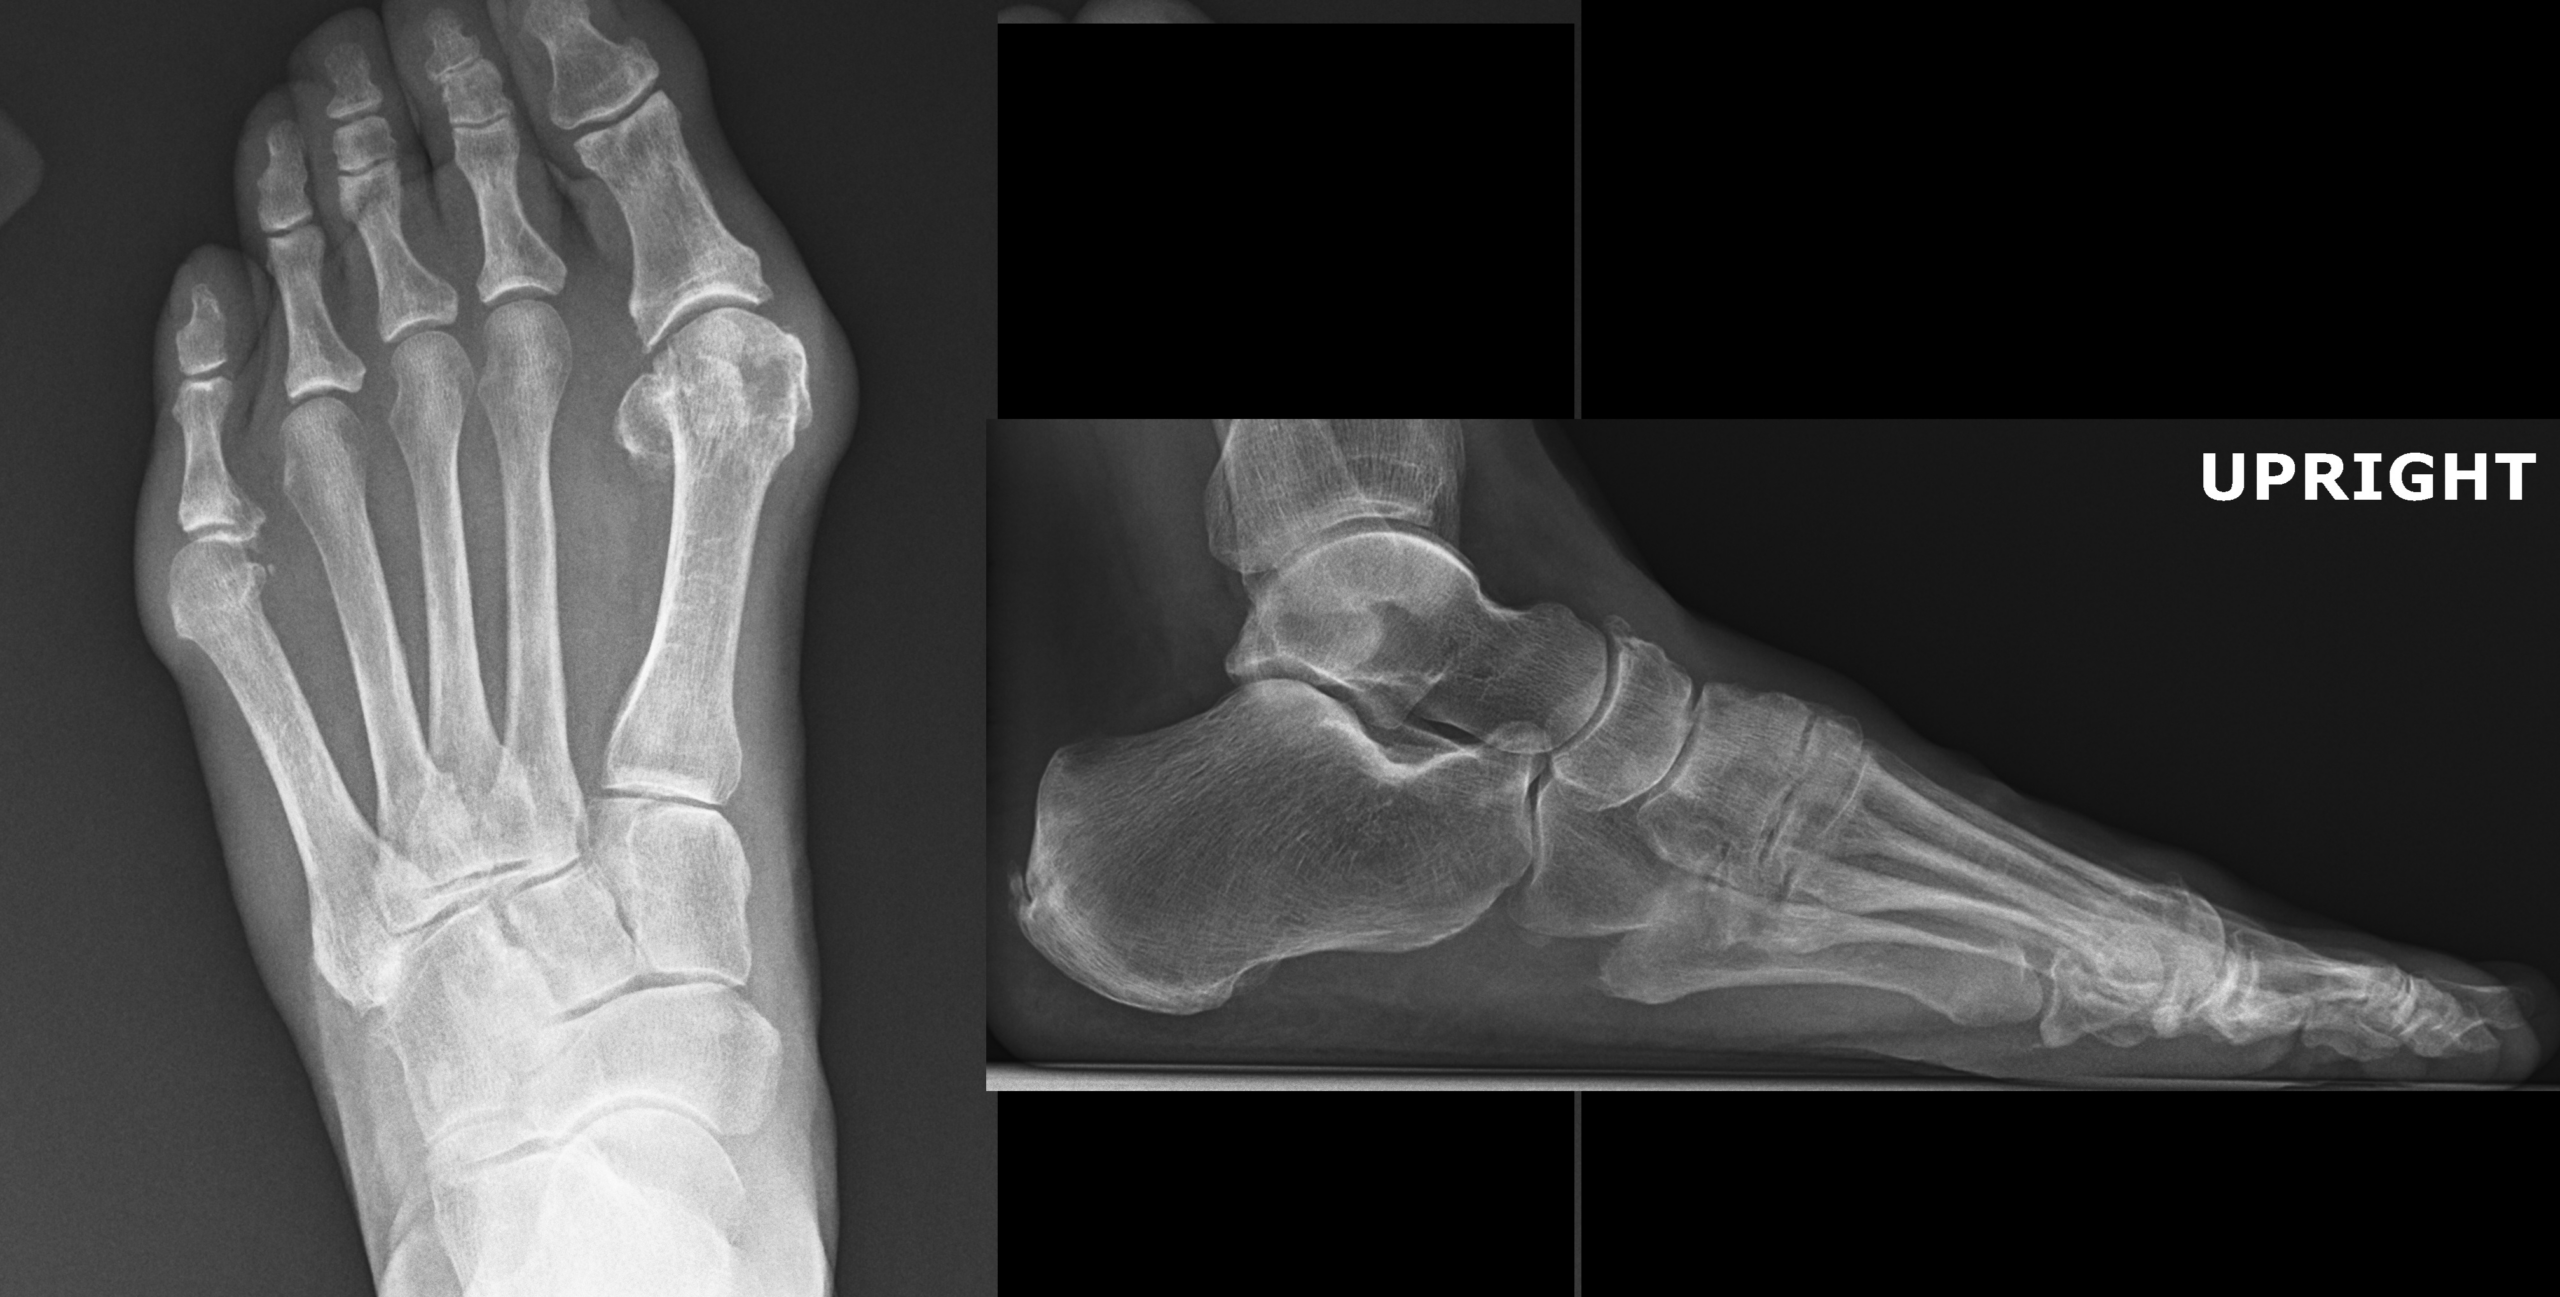

At the completion of the Urgent Care Orthopedic Essentials II PAs should have a better understanding of the diagnosis and treatment of benign tumors of the hand, forearm fractures, sternal fractures, right hip fractures, elbow stiffness after fracture, arthritis of the foot and ankle, management of partial and full thickness rotator cuff tears, lumbar spine arthritis, shoulder instability, symptomatic osteochondromas, fractures of the humerus, fractures of the foot and ankle, cause of pain in the hand and wrist, fractures of the coracoid, lateral and medial elbow tendinitis, tendinitis around the knee, finger dislocations, fractures of the cervical spine, complications of finger fractures, foot drop, management of foreign bodies, mallet fingers, causes of hip pain, ligament injuries of the hand and wrist, and deformities of the fingers.

An 80 year old female presents to your office with a left ring finger deformity after a fall one week ago. She initially went to urgent care and xrays were unremarkable for a fracture (Figures 1 and 2). A photo of her left ring finger is shown in figure 3. On physical exam the left ring finger is in hyperextension at the PIP joint and flexion at the DIP joint. She able to flex her PIP joint with full motion. What is the best treatment option?